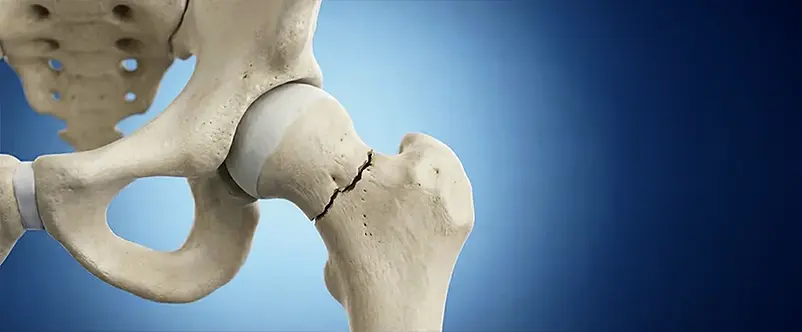

Traumatologiastaff@2026-03-11T08:00:58+00:00 Traumatologia Frattura del Femore, Frattura del Piatto Tibiale, Frattura della Rotula